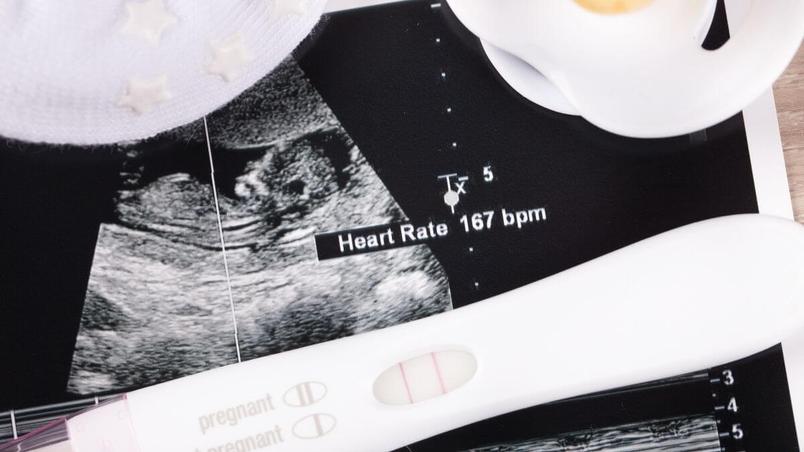

Oh yes! One of the highlights of the 12-week ultrasound is potentially hearing baby’s heartbeat. This will sound like a little flutter, beating at around 120-160 beats per minute – enough to bring a happy tear to the eye.

Your 12-week ultrasound may also be the very first time you get a glimpse of baby (pics included) and hear their heartbeat — cue the waterworks!